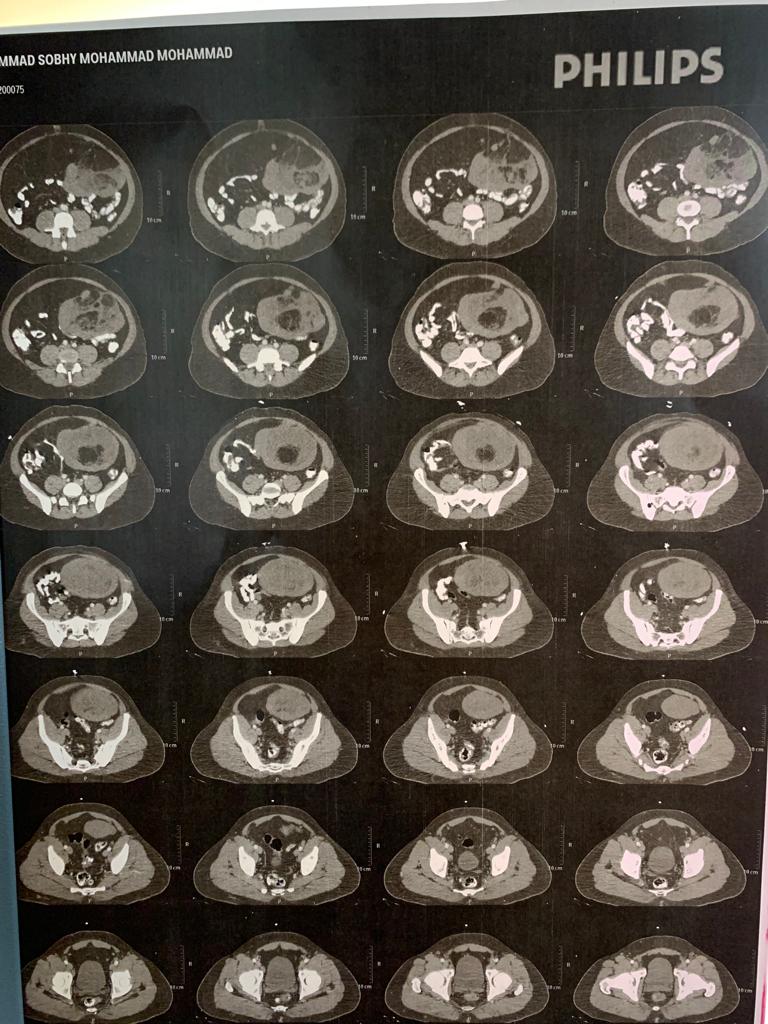

وأثناء إجراء الفحوصات الطبية تلاحظ للأطباء حجم البطن الكبير، لذا تم عمل أشعة فوق صوتية خوفا من وجود نزيف داخلى ناتج عن الحادثن وتبين وجود ورم كبير بتجويف البطن وهذا هو السبب المباشر لزيادة الحجم، وبعد الاطمئنان على حالته الصحية وتلقيه العلاج المناسب للكدمات التى أصيب بها نتيجة للحادث تم تحويله بشكل فورى إلى مرکز جراحة الجهاز الهضمى.

وخلال تواجده بالعيادة الخارجية تم مناظرته على الفور وتم عمل الفحوصات اللازمة والتي أكدت وجود ورم كبير بالبطن لم يكن له أي أعراض تذكر سوی ازدياد حجم البطن وتم تحضير الحالة لإجراء جراحة فورية.

وأثناء الجراحة وجد أن الورم نشأ من جدار المعدة السفلى منطقة البواب، وتمتد بشكل كبير يحتل معظم تجويف البطن الداخلى عدا منطقة الخوص ،ويضغط بشكل كامل على جميع الأعضاء الداخلية بشكل كبير.

وبعد 4 ساعات من العمل المتواصل نجح الفريق الجراحى فى استئصال هذا الورم بأمان، وقد كان حجم 45×52 × 65 ووزنه ٧٨٧٢ جم، وبعد الاطمئنان على حالة المريض ما بعد الجراحة تم نقله إلى العناية المركزة لاستكمال العلاج.